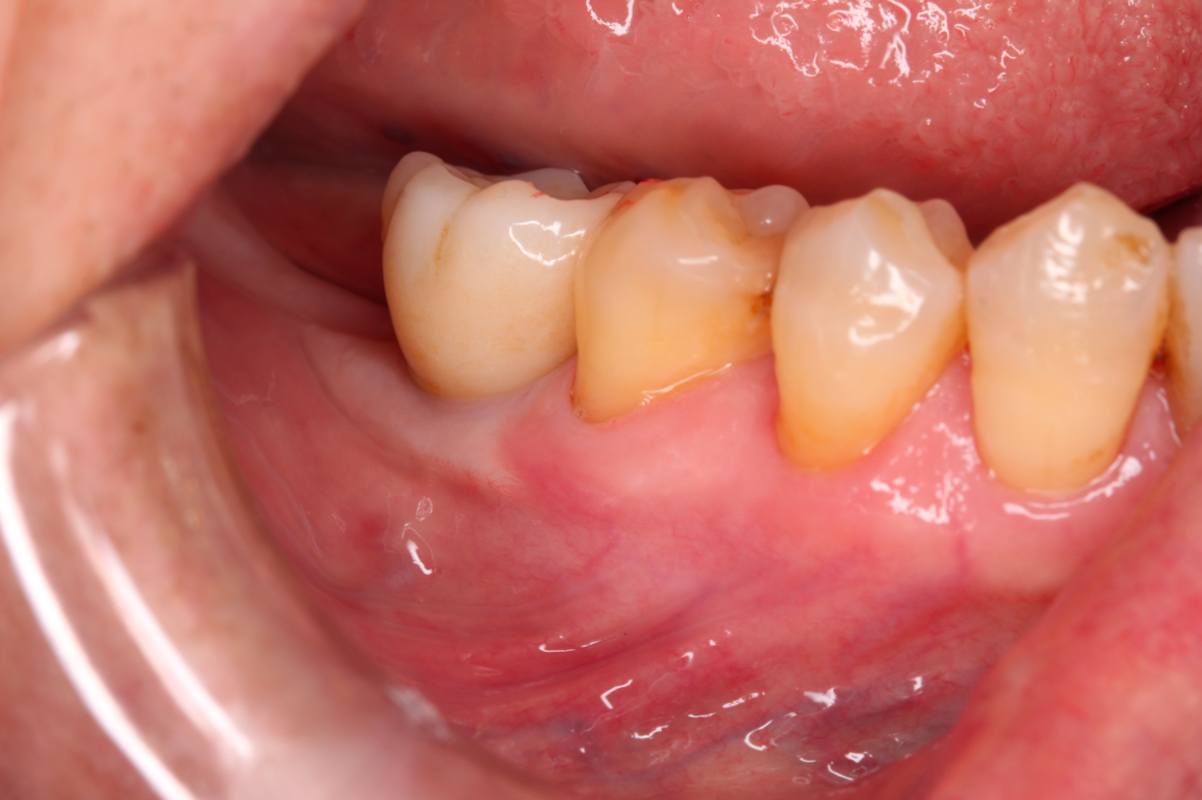

【治療醫師:林農翔 醫師】 植牙的角化牙齦移植術 植牙的角化牙齦移植術是一種在植牙手術中常見的程序,旨在改善患者缺牙區域的牙齦狀態,提高植牙的成功 …